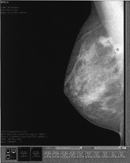

GE横河メディカルシステム(株)は,フルデジタルマンモグラフィ「Senographe 2000D」専用のコンピュータ検出支援システム(CAD)「セノグラフ 2000D 用 CAD」を発売した。2002年4月に米国で販売されて以来,臨床的有用性が高く評価され,現在,米国における「Senographe 2000D」の総稼働台数450台の1/3にあたる約150台に搭載されている。すでに「Senographe 2000D」を導入している施設のほか,デジタルマンモグラフィを新規導入予定の施設向けにはCADを搭載した製品を販売。初年度,国内販売台数20台を目指す。

「Senographe 2000D」の撮影画像上で,乳がんの疑いのある「細かい明点の集まり(微小石灰化)」や「白い影(腫瘤影)」を自動検出。微小石灰化を「早v,腫瘤影を「*」の記号でモニタ上に表示する仕組みとなっている。読影医は通常の読影後,「セノグラフ 2000D 用 CAD」を用いて必要に応じて記号を表示することで,見落としが減り,初期段階の微小ながんを迅速かつ正確に読影できる。また,早期発見率が向上することで,生存率を高めることが可能となり,トータルでの治療費抑制にもつながる。